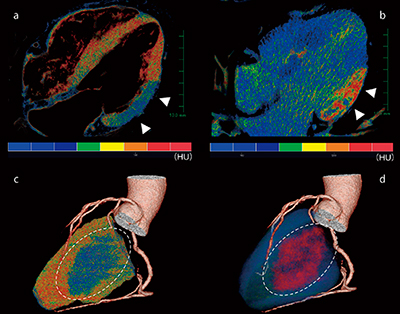

症例提示

症例は,持続する胸痛により当院に救急搬送された60歳代,男性。冠動脈解析の結果,左回旋枝(LCX)低形成,右冠動脈(RCA)優位の冠動脈であり,LAD#6に混合型プラークを認め同部位の有意狭窄が疑われた。しかし,心筋灌流評価を行った結果,LCXの灌流域である側壁に貫壁性の造影低下領域を検出した(図2,図3 a,c)。そこで,造影低下領域の冠動脈を再確認するとLCX#13完全閉塞であることが判明した。この結果から,LCXの完全閉塞による心筋梗塞であると診断され経皮的冠動脈形成術(PCI)が施行された。

本症例では,PCI施行後に心電図同期単純CTを撮影した。PCI直後の単純CTで認められる造影効果は,心筋障害を反映している2)。この撮影により,梗塞巣の確認とともに局在を観察し,心筋バイアビリティを評価することが可能である。この評価にも,心筋灌流評価に用いるカラーマップを使用することで,遅延造影領域を明瞭に描出できる。本症例では,心臓CTで認めた灌流異常領域と一致する領域に,PCI後単純CTで貫壁性の遅延造影を認めた(図3 b,d)。これより,心臓CTで描出された低CT値領域が灌流異常領域を示していることが確定できる。

図3 心筋性状評価

a:心臓CT四腔像

b:PCI後単純CT四腔像

c:心臓CT冠動脈と心臓CT心筋の融合画像

d:心臓CT冠動脈とPCI後単あ純CT心筋の融合画像